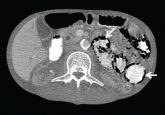

ArticlePneumatosis cystoides intestinalis: Is surgery always indicated?Author:Swapna Vattikuti, MDPublish date: March 1, 2015This disease is usually benign. However, evidence of necrosis or pneumoperitoneum warrants immediate surgery.Read More